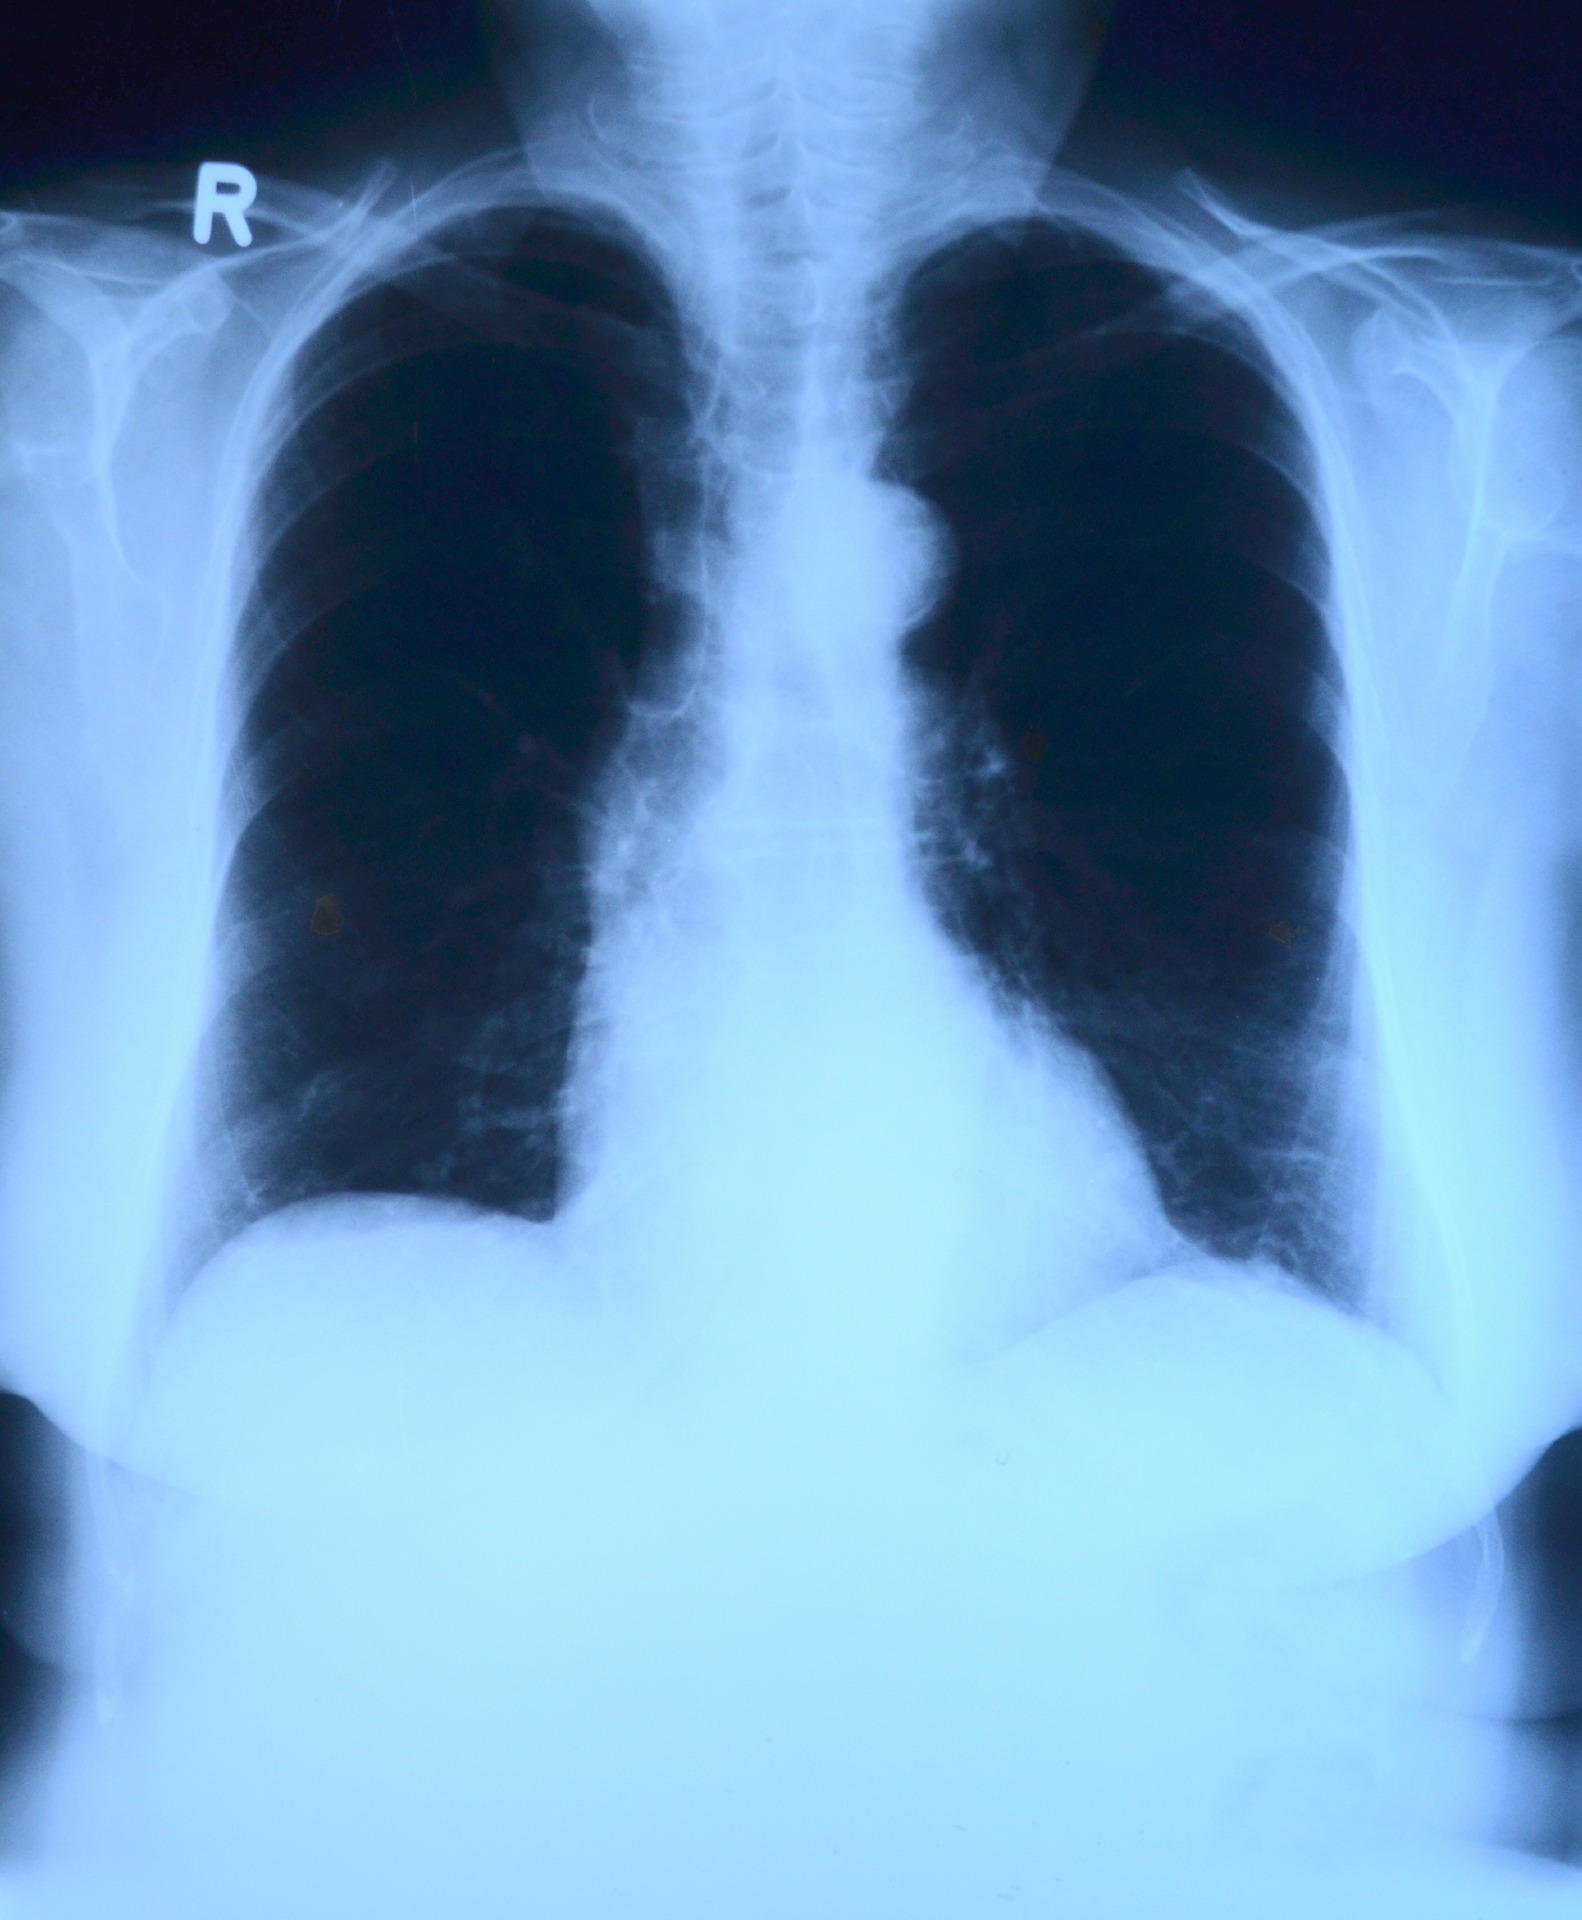

ภาวะลิ่มเลือดอุดตันในปอดมักเกิดจากลิ่มเลือดที่อุดตันบริเวณหลอดเลือดขา ซึ่งเป็นหลอดเลือดที่เชื่อมต่อกับหัวใจข้างขวาและปอด จากนั้นลิ่มเลือดได้หลุดไปอุดตันที่ปอดตามลำดับ และโดยส่วนมากลิ่มเลือดอุดตันมักเกิดที่บริเวณใดบริเวณหนึ่งก่อนเข้าสู่ปอด โดยจะเจ็บบริเวณที่ลิ่มเลือดอุดตัน

เนื่องจากลิ่มเลือดไปยังเยื่อหุ้มปอดมีตัวรับความรู้สึก ทำให้ขณะหายใจรู้สึกเจ็บ และถ้าหากลิ่มเลือดอุดตันในปอดเกิดขึ้นฉับพลัน อาจมีอาการเหนื่อยและเจ็บหน้าอกร่วมด้วย แต่เป็นอาการไม่จำเพาะเจาะจง อาจทำให้การวินิจฉัยโรคผิดพลาดได้ เนื่องจากมีอาการคล้ายโรคหัวใจ โรคหอบหืด